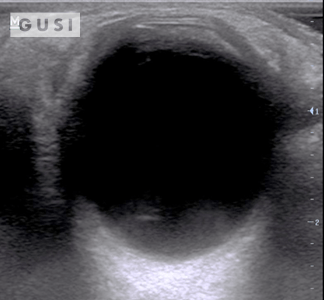

|

During the 2017 World Taekwondo Championships in Muju, Korea, a 30-year-old female athlete from Hong Kong was kicked in her left eye by an opponent. She reported fluctuating vision accompanied by pain during eye movement. A POCUS examination of the affected eye indicated a vitreous hemorrhage, with no evidence of lens subluxation or globe rupture.

On the ultrasound, as the athlete moved her eyes laterally, the hemorrhage (denoted by a white arrow) exhibited a swirling pattern within the globe, consistent with her eye movement. The athlete was promptly referred to a specialized medical center for an ophthalmology consultation, where the diagnosis of vitreous hemorrhage was confirmed. The patient was subsequently discharged from the Emergency Department with specific precautionary measures.